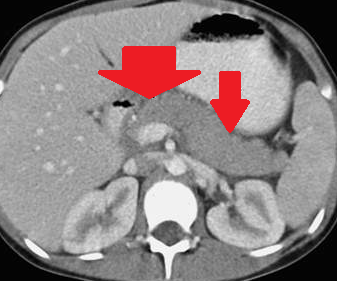

Multiple hepatic abscesses in other patients with cholecystocolic fistulas (Courtesy Dr. V. Penopoulos)